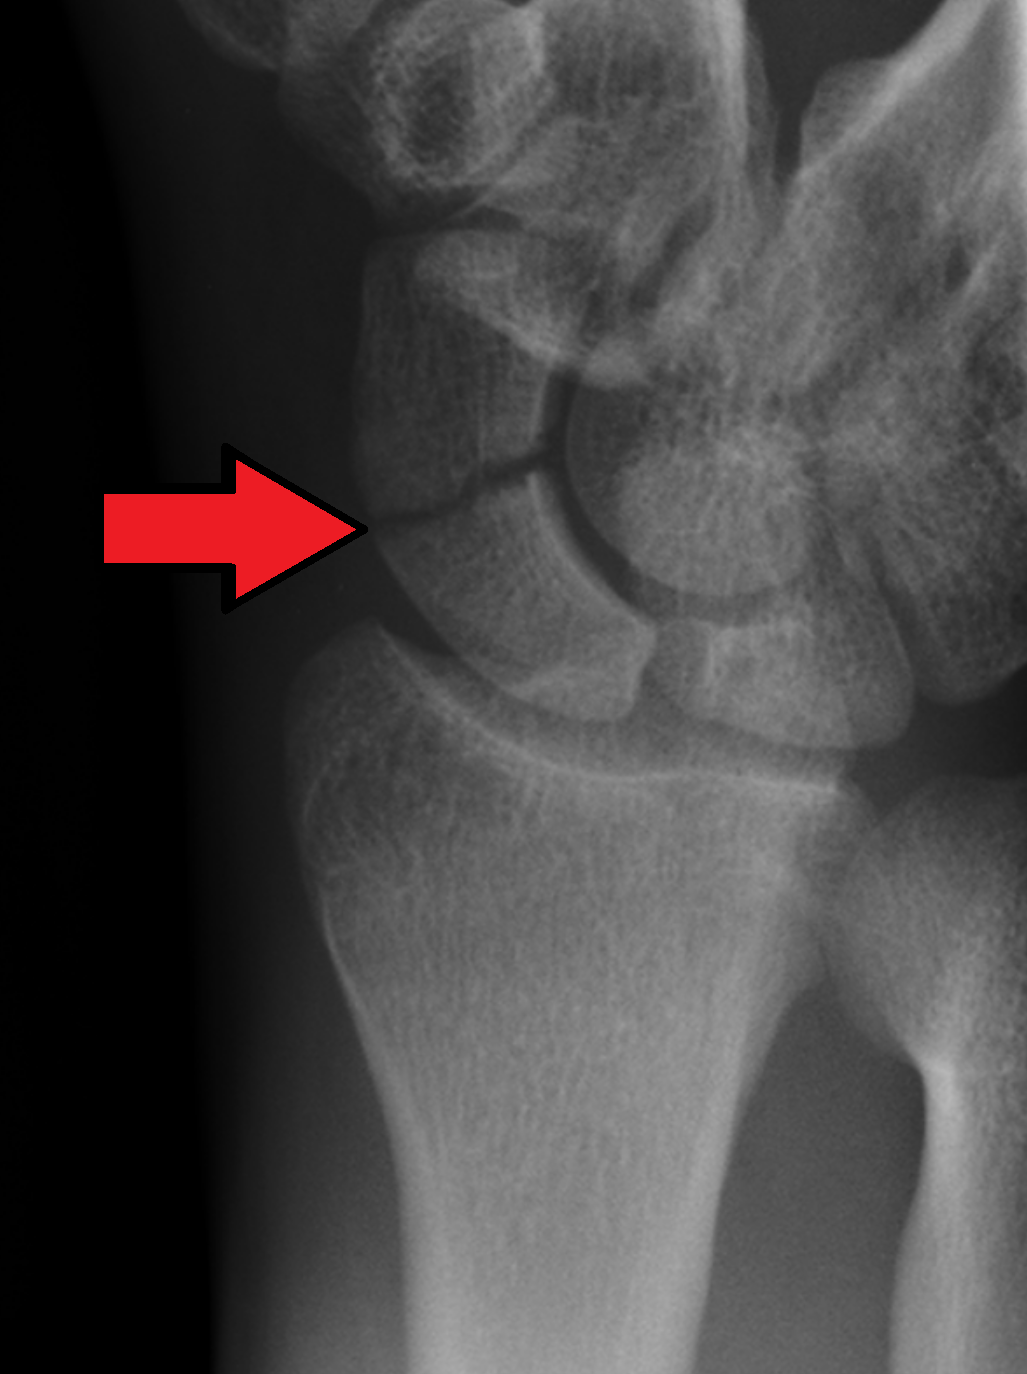

Symptoms of a scaphoid fracture include: Pain. Swelling. Tenderness. Inability to move your wrist. Bruising or discoloration. A deformity or bump that’s not usually on your wrist.